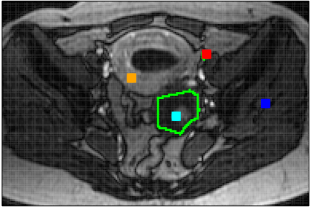

The real DCE-MR image sequences of two female pelvis with ovarian tumors [Thomassin-Naggara et al., 2012] consist of, respectively, 130 and 107 images on a grid of 192x128 voxels, acquired over 305 seconds, see Figure 3. With the delayed injection of the contrast agent bolus, their ( and 10) first images show only the grey level baseline up to the noise level. In both sequences, a ROI around the tumor has been manually drawn by an experienced radiologist after acquisition.

The two real DCE-MR image sequences have been fully segmented into homogeneous regions that are highly consistent with anatomical structures as shown in Figure 13. The smaller is, the more details in anatomical structures can be observed in image sequence. This is highlighted (see Fig. 14) in the ROIs defined by the squares that contain the manually segmented ROIs, shown in black on Figure 13. The corresponding estimated TCs inside each cluster within the ROI together with their corresponding size are shown in Figure 15. By segmenting the full DCE sequence, these estimated TCs are obtained by averaging TCs which do not necessarily belong to the ROI but do belong to the same homogeneous cluster. As a benefit, the SNR observed for these estimated TCs is strongly improved, providing a real opportunity for further analysis and comparisons. From these figures, one can clearly understand the advantages of DCE-HiSET. It is indeed providing a piecewise constant representation of the DCE image sequence in functionally homogeneous regions, where controls the size of the pieces and the functional discrepancy between them.

Patient 1

Patient 2